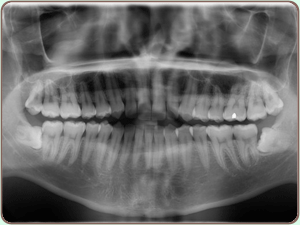

Digital X-Ray

Digital x-rays are computer-generated images. These images require up to 90% less radiation than conventional x-rays. Instead of using the traditional silver-oxide x-ray film that must be developed and fixed using caustic and environmentally damaging chemicals. Digital x-rays take pictures via a storage phosphor screen and through the use of a laser and computer immediately transmit a picture of the tooth to a video monitor in the treatment room.